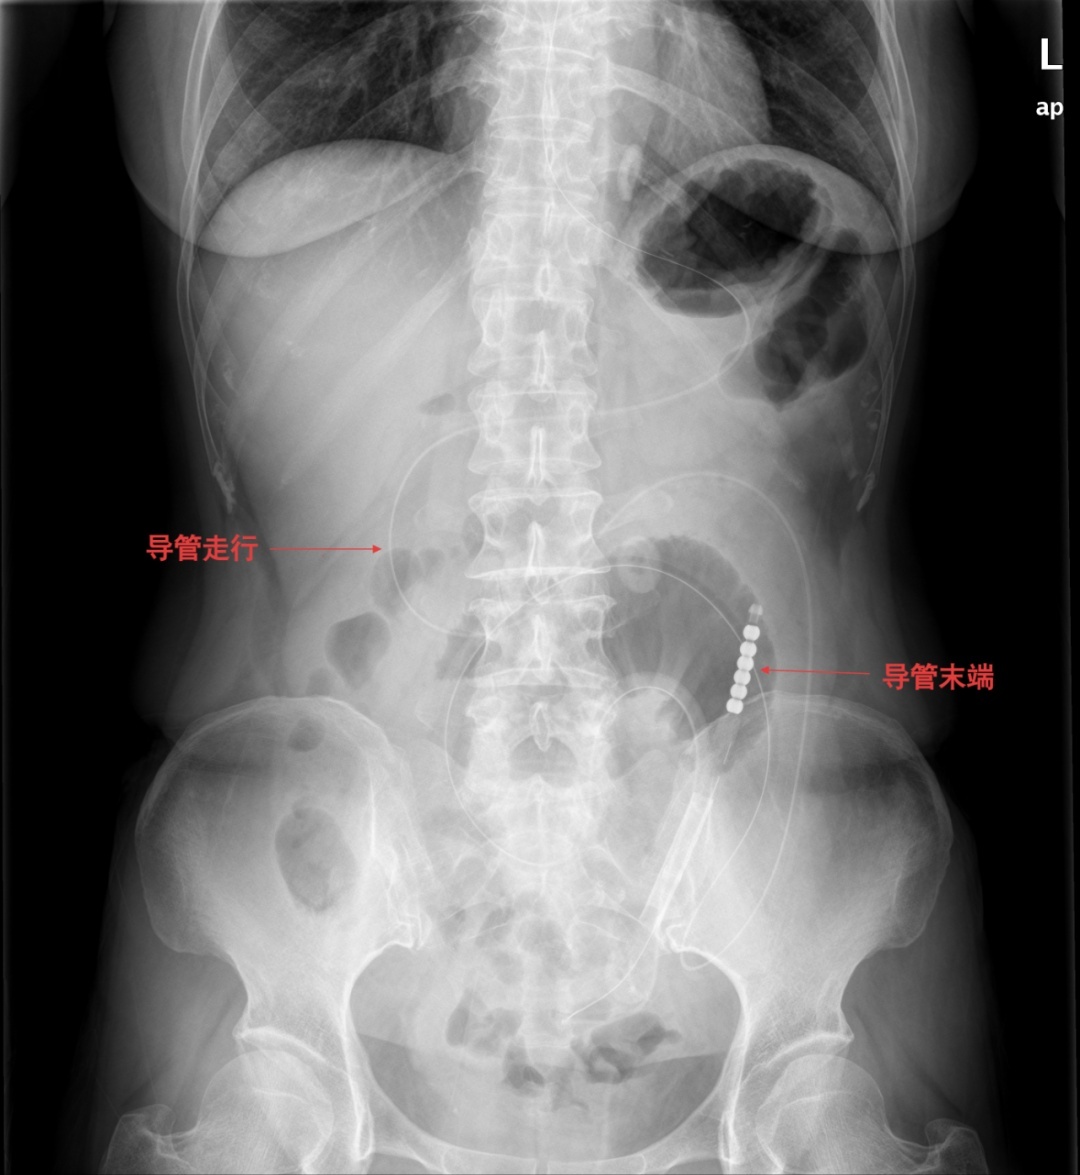

▲腹部CT所见

入院后,完善相关检查,腹部立位平片提示肠管扩张,可见多个液气平面,结合病史考虑术后肠梗阻。经综合评估,决定先行保守治疗,在胃肠外科和疝外科刘奇副主任医师团队协作下,为患者置入肠梗阻导管。置管后,患者腹胀、腹痛症状明显缓解,胃肠减压引流通畅,肠鸣音逐渐恢复。经精心护理及营养支持,患者肛门排气排便恢复正常,复查腹部平片示肠管扩张较前明显改善,无液气平面。病情持续好转,顺利出院。